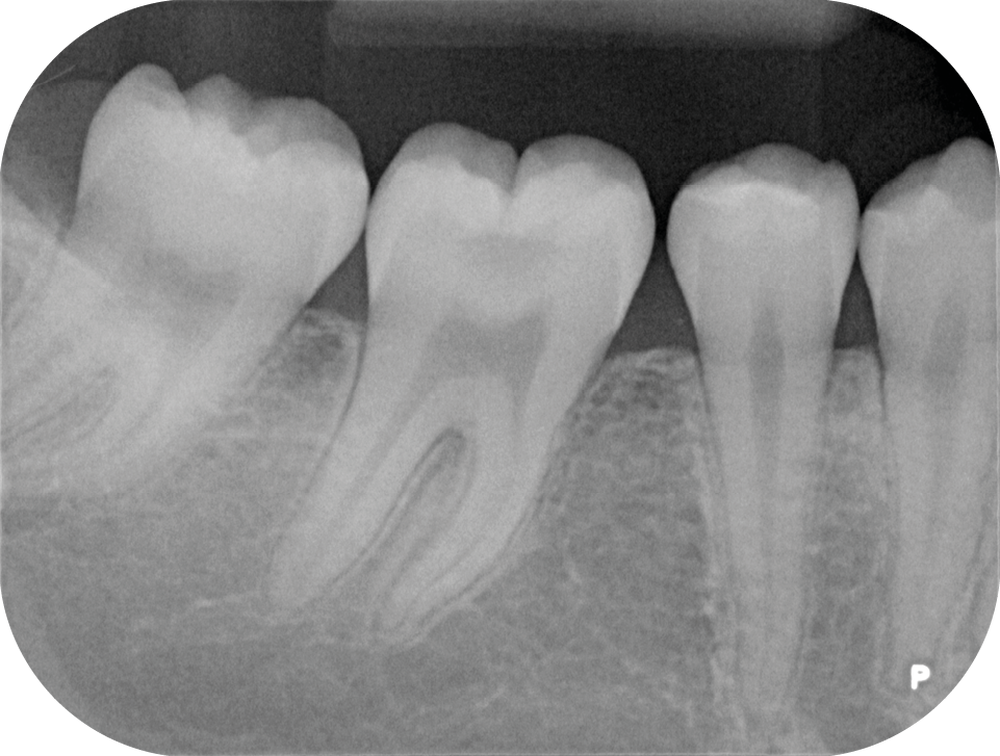

Nous détaillons la technique à travers le cas d’une jeune fille de 18 ans présentant des lésions carieuses sur quatre dents (fig. 1 à 14).